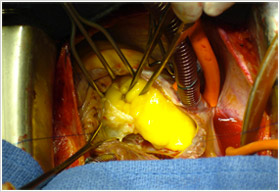

Elle se présentent sous deux aspects : la forme « gélatineuse » qui est à l’origine de complications emboliques systémiques au niveau des membres et du cerveau et la forme « fibreuse » arrondie et ferme qui est à l’origine des enclavements dans l’orifice mitral qui sépare l’oreillette et le ventricule gauche.

Les symptômes (essoufflements, toux, malaises voire syncope surtout aux changements de position) sont liés à la taille de la tumeur (qui varie de 1 à 8 cm de diamètre), à sa localisation par rapport à l’orifice mitral et aux veines pulmonaires, à son aspect (gélatineux ou fibreux) ainsi qu’à sa mobilité (tumeur villeuse ou pédiculée).

Sous circulation extracorporelle, le cœur et les poumons sont arrêtés. On ouvre l’oreillette gauche et on procède à l’ablation de l’intégralité de la tumeur sans la fractionner. On résèque la zone d’implantation qui siège le plus souvent au niveau de la cloison entre les deux oreillettes et qui est refermée par un patch de péricarde ou de Dacron.

On explore les quatre cavités cardiaques, oreillettes et ventricules à la recherche d’une autre localisation tumorale. On explore aussi les valves cardiaques qui peuvent avoir été lésées par les mouvements de la tumeur.